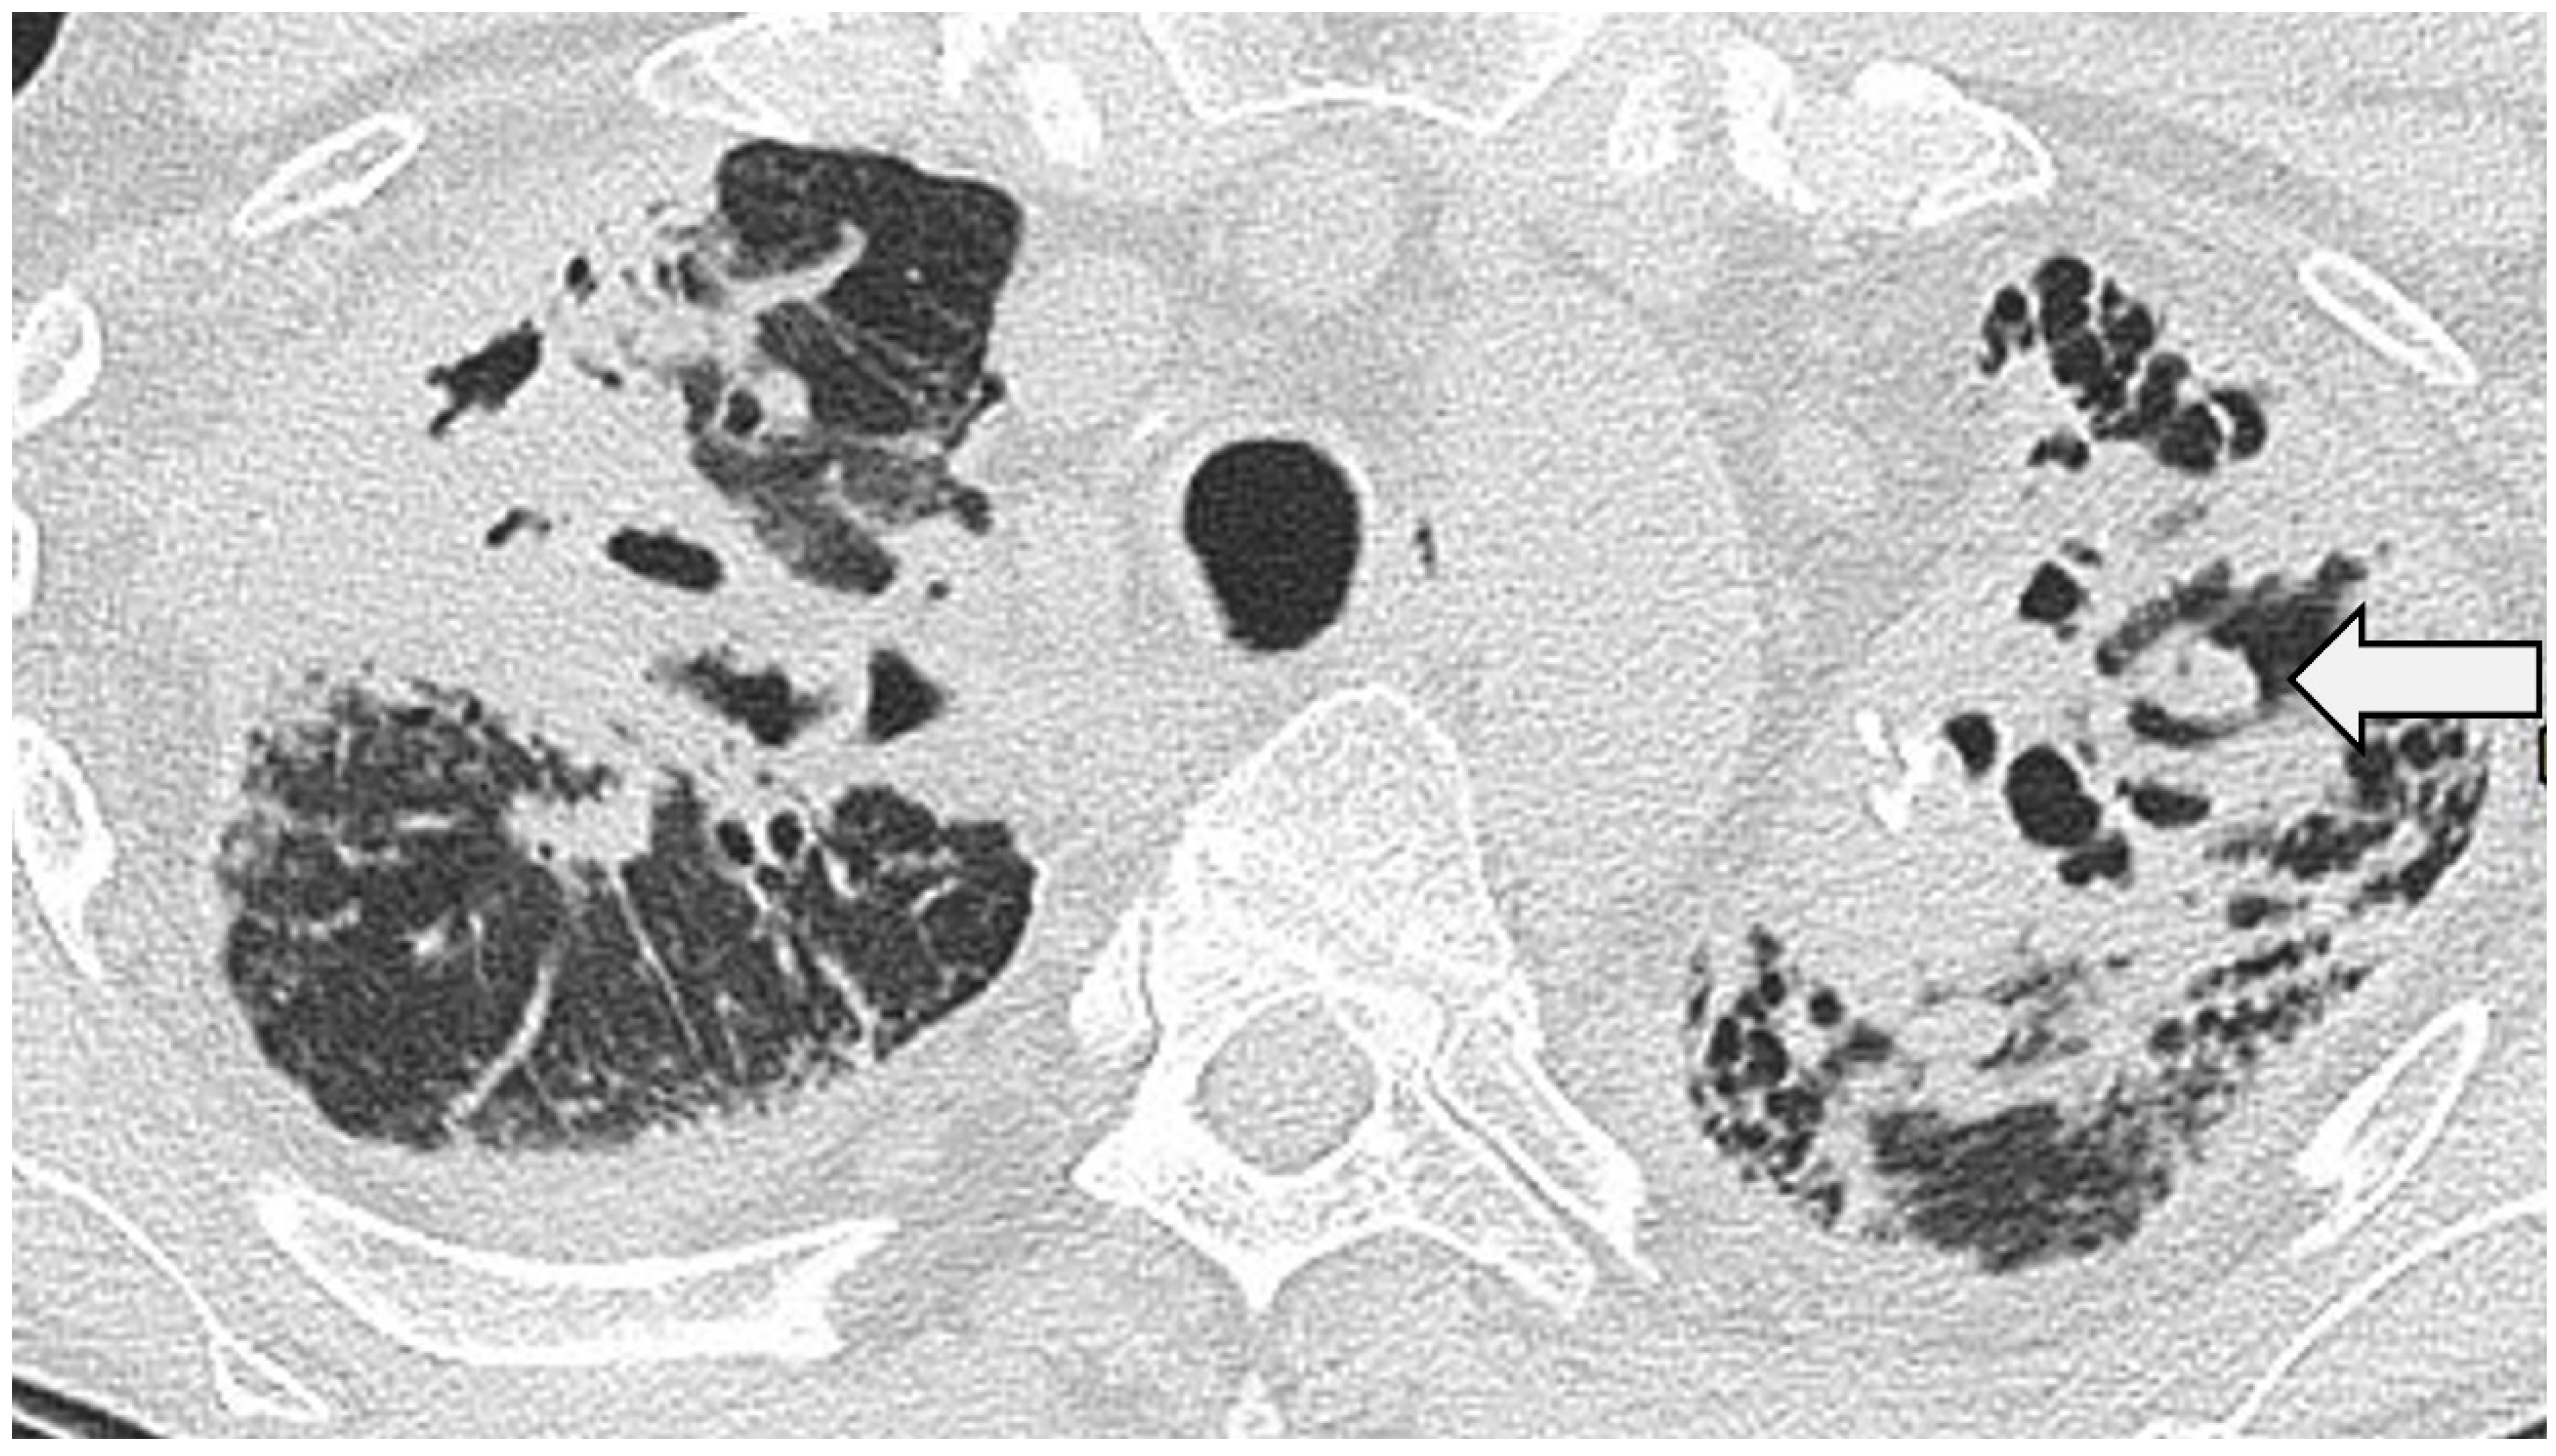

3.6. Pulmonary Fibrosis

Figure 6.

CT through the upper zones in a 61-year-old patient with pulmonary sarcoidosis. There is extensive disease with bronchocentric fibrosis manifest as a pattern of the consolidated lung. Note that in the left upper lobe, there is evidence of cavitation with a small aspergilloma (arrow).

4.1. Cavitation

Cavitation in sarcoidosis is uncommon and seen in ~10% of patients with advanced disease [78]. Primary cavitary sarcoidosis is estimated to affect around 2% and, again, tends to occur in patients with severe, ‘active’ sarcoidosis [79]. Superimposed infection (particularly with fungi or mycobacterial species) should always be considered in this context.

4.2. Fungal Colonisation

Fungal colonisation, most commonly with Aspergillus species, complicates between 3 and 12% of sarcoidosis cases with fibrocavitary (or fibrobullous) disease [80]. The radiologic manifestation might be in the form of a simple aspergilloma within a densely fibrotic lung, within a pre-existing bulla or grossly ectatic airway [81,82] (Figure 7). Serological and biochemical markers may be of value in diagnosis [83,84]. In a minority of patients, untreated fungal colonisation will lead, over time, to chronic and extensive fibrotic destruction [81].